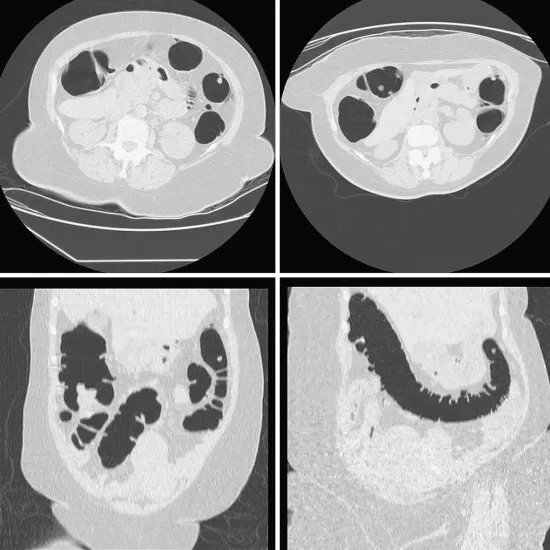

CT colonography (Computed Tomography Colonography) is an imaging scan. It uses a low dose of radiation to check the colon (large bowel) and rectum (back passage).  It produces images of an interior view of the large intestine. It is also known as virtual colonoscopy. The doctor recommends this scan to diagnose/detect tumors and other conditions such as polyps that affect the colon and rectum.

CT (Computed tomography) screening of the Colonography is a non-invasive radiology test used to evaluate the condition of the colon, rectum and surrounding tissue. CT Colonography is done to look for the conditions of the colon, rectum and the surrounding area.